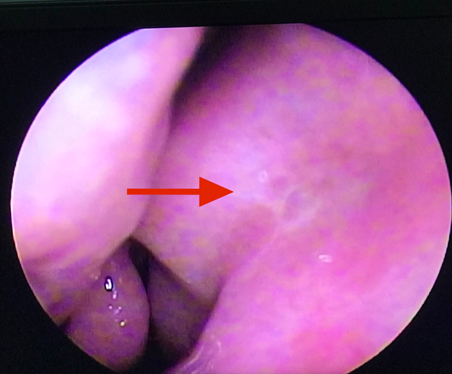

Vừa qua khoa Mắt - Bệnh viện Đa khoa tỉnh vừa tiếp nhận vầ điều trị Bệnh nhân nữ 49 tuổi vào viện vì xuất hiện khối sưng nề góc trong mắt trái kết hợp chảy mủ và chảy nước mắt nhiều. Tại đây bệnh nhân được xác định chẩn đoán Mắt trái: Viêm mủ túi lệ/ Tắc lệ đạo, bệnh nhân đã được điều trị nội khoa tích cực, triệu chứng lâm sàng giảm dần. Khoa Mắt và khoa Tai mũi họng đã kết hợp phẫu thuật cho bệnh nhân bằng phương pháp Nối thông túi lệ mũi bằng nội soi. Phẫu thuật này đã tạo đường thông trực tiếp từ túi lệ sang khoang mũi nhằm dẫn nước mắt từ mắt sang mũi. Sau phẫu thuật 2 ngày, các triệu chứng lâm sàng của bệnh nhân thuyên giảm và được ra viện sớm.

Hình 3. Ống Silicon được từ 2 lệ quản xuống mũi